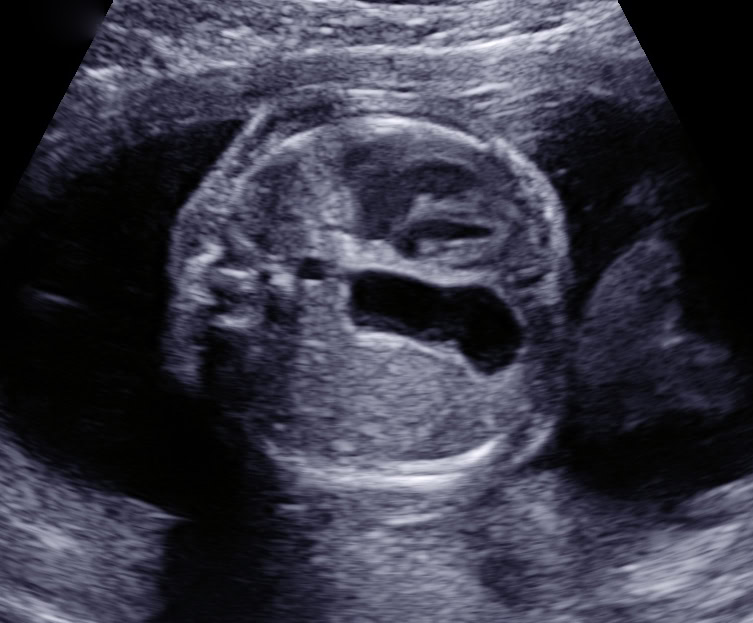

Wasseransammlung im fetalen Bauch (Aszites)

Fetus in der 23. SSW mit viel Platz durch zuviel Fruchtwasser